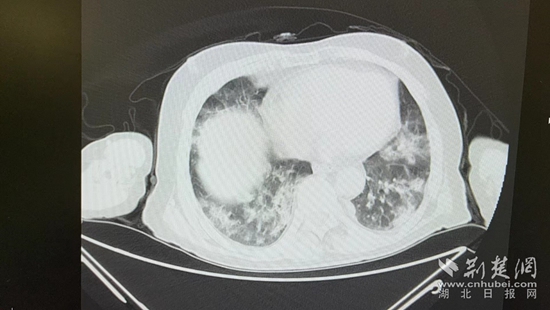

病情的突然惡化,會(huì)不會(huì)與近期的新冠病毒感染有關(guān)?雖然家屬反映,曾多次在家自測抗原正常,但徐濤還是力排眾議,說服老人進(jìn)行核酸檢測和肺部CT檢查。結(jié)果顯示核酸陽性,60%白肺,結(jié)合老人的表現(xiàn),這正是一例典型的老年人“沉默性肺炎”。

胸部CT片。通訊員 供圖